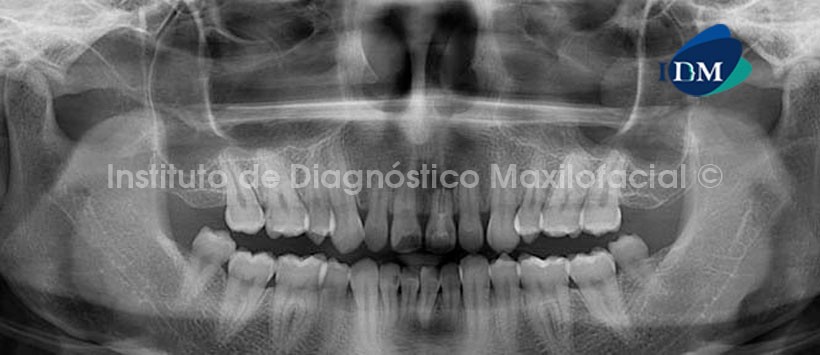

En la radiografía panorámica (Fig.1) se observa a la Pieza 2.1 con obturación cameral, el ensanchamiento del espacio periodontal; además de la obturación parcial del conducto radicular y a la vez sobrextendido; y un proceso osteolítico periapical el cual, probablemente, ha inducido la reabsorción del tercio apical radicular. También se observa un probable proceso de reabsorción radicular externa a nivel apical en las piezs 1.1 y 1.2; las piezas 3.8 y 4.8 extruidas y la ausencia de las piezas 1.4, 1.8, 1.5, 2.8.